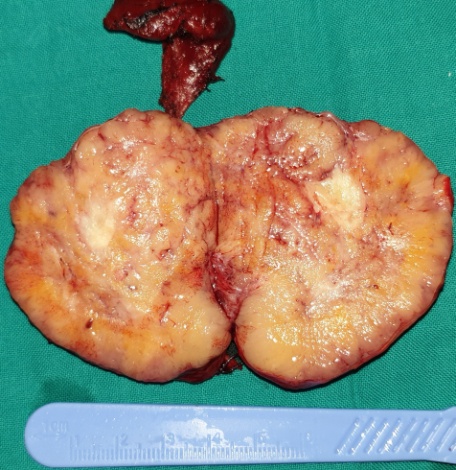

Cross section of the surgical specimen. Areas of necrosis are evident (Courtesy Dr. V. Penopoulos)